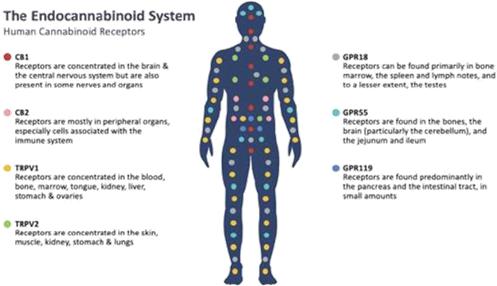

Continue to explore the potential of a wide array of rare cannabinoids and their analogs/variants to treat diseases based on our significant history in cannabinoid research and lead drug candidate identification.

Individual cannabinoids affect a range of different receptors in the human body, including, but not limited to, known endocannabinoid receptors. As such, they are responsible for a wide variety of pharmacological effects. However, due to the limited research into these varying effects, a full understanding of the role of each cannabinoid compound remains elusive. As a company, we have been formally investigating the utility of cannabinoids in treating disease for over 5 years.

Cannabinoid receptors are found throughout the body and are involved in many different functions, such as pain perception, memory, immune function and sleep. Cannabinoids act as messengers that bind to cannabinoid receptors, as well as other receptors, signaling the endocannabinoid system into action. The relevance of the endocannabinoid system on many important physiological processes has made cannabinoids an important target to potentially treat a number of diseases and symptoms.

Two cannabinoid receptors in the human body are the endocannabinoid receptor 1 (CB1), which is more significant to the central nervous system, and endocannabinoid receptor 2 (CB2), which is more common with the immune system. Scientific literature suggests that CBN has a greater effect on the immune system than on the central nervous system; however, information on the effects of CBN on the endocannabinoid system is limited. We continue to research the effects of CBN and how it interacts and modulates receptors in the body.

Significant investigation is currently underway to determine the role of cannabinoids in affecting other receptor systems in the human body. Extensive preclinical testing undertaken by us has identified several unique properties of CBN that outperformed both THC and CBD in various disease-related assays and models. CBN can act with higher potency when interacting with some receptor systems in the body, while acting with lower potency for others.